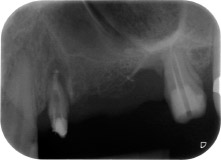

апикално-периодонтална лезия на зъб 24

Фиг. 1: 58-годишна пациентка. Предоперативната рентгенография показва апикално-периодонтална лезия на зъб 24 и хоризонтална загуба на алвеоларна кост във втори квадрант.

58-годишна пациентка се оплаква от болка и повишена подвижност в нейния мост върху зъб 24 с функция на абатмънт. На лице е периодонтално възпаление с дълбочина на джоба 7 mm мезиобукално и повече от 12 mm дистално, както и включена 3 градусова фуркация. Освен това, рентгенографията показва обширна периодонтална лезия около апикалната зона на (друго място) предварително ендодонтски обработен зъб 24 (Фиг. 1).

Една година по-късно, зъби 25 и 26 са екстрахирани в следствие на травма и поради ендо-перио причини, преди поставянето на моста. Комбинирана ендо-перио лезия е диагностицирана за зъб 24 от неясна етиология. Пациентката иска да задържи нейния мост с абатмънт на зъби 24 и 27 и не приема окончателна, подвижна протеза. По този начин, взаимно решихме да положим всички усилия да запазим и двата зъба, въпреки лошата прогноза за тях, която е базирана на рентгенографски и клинични резултати.